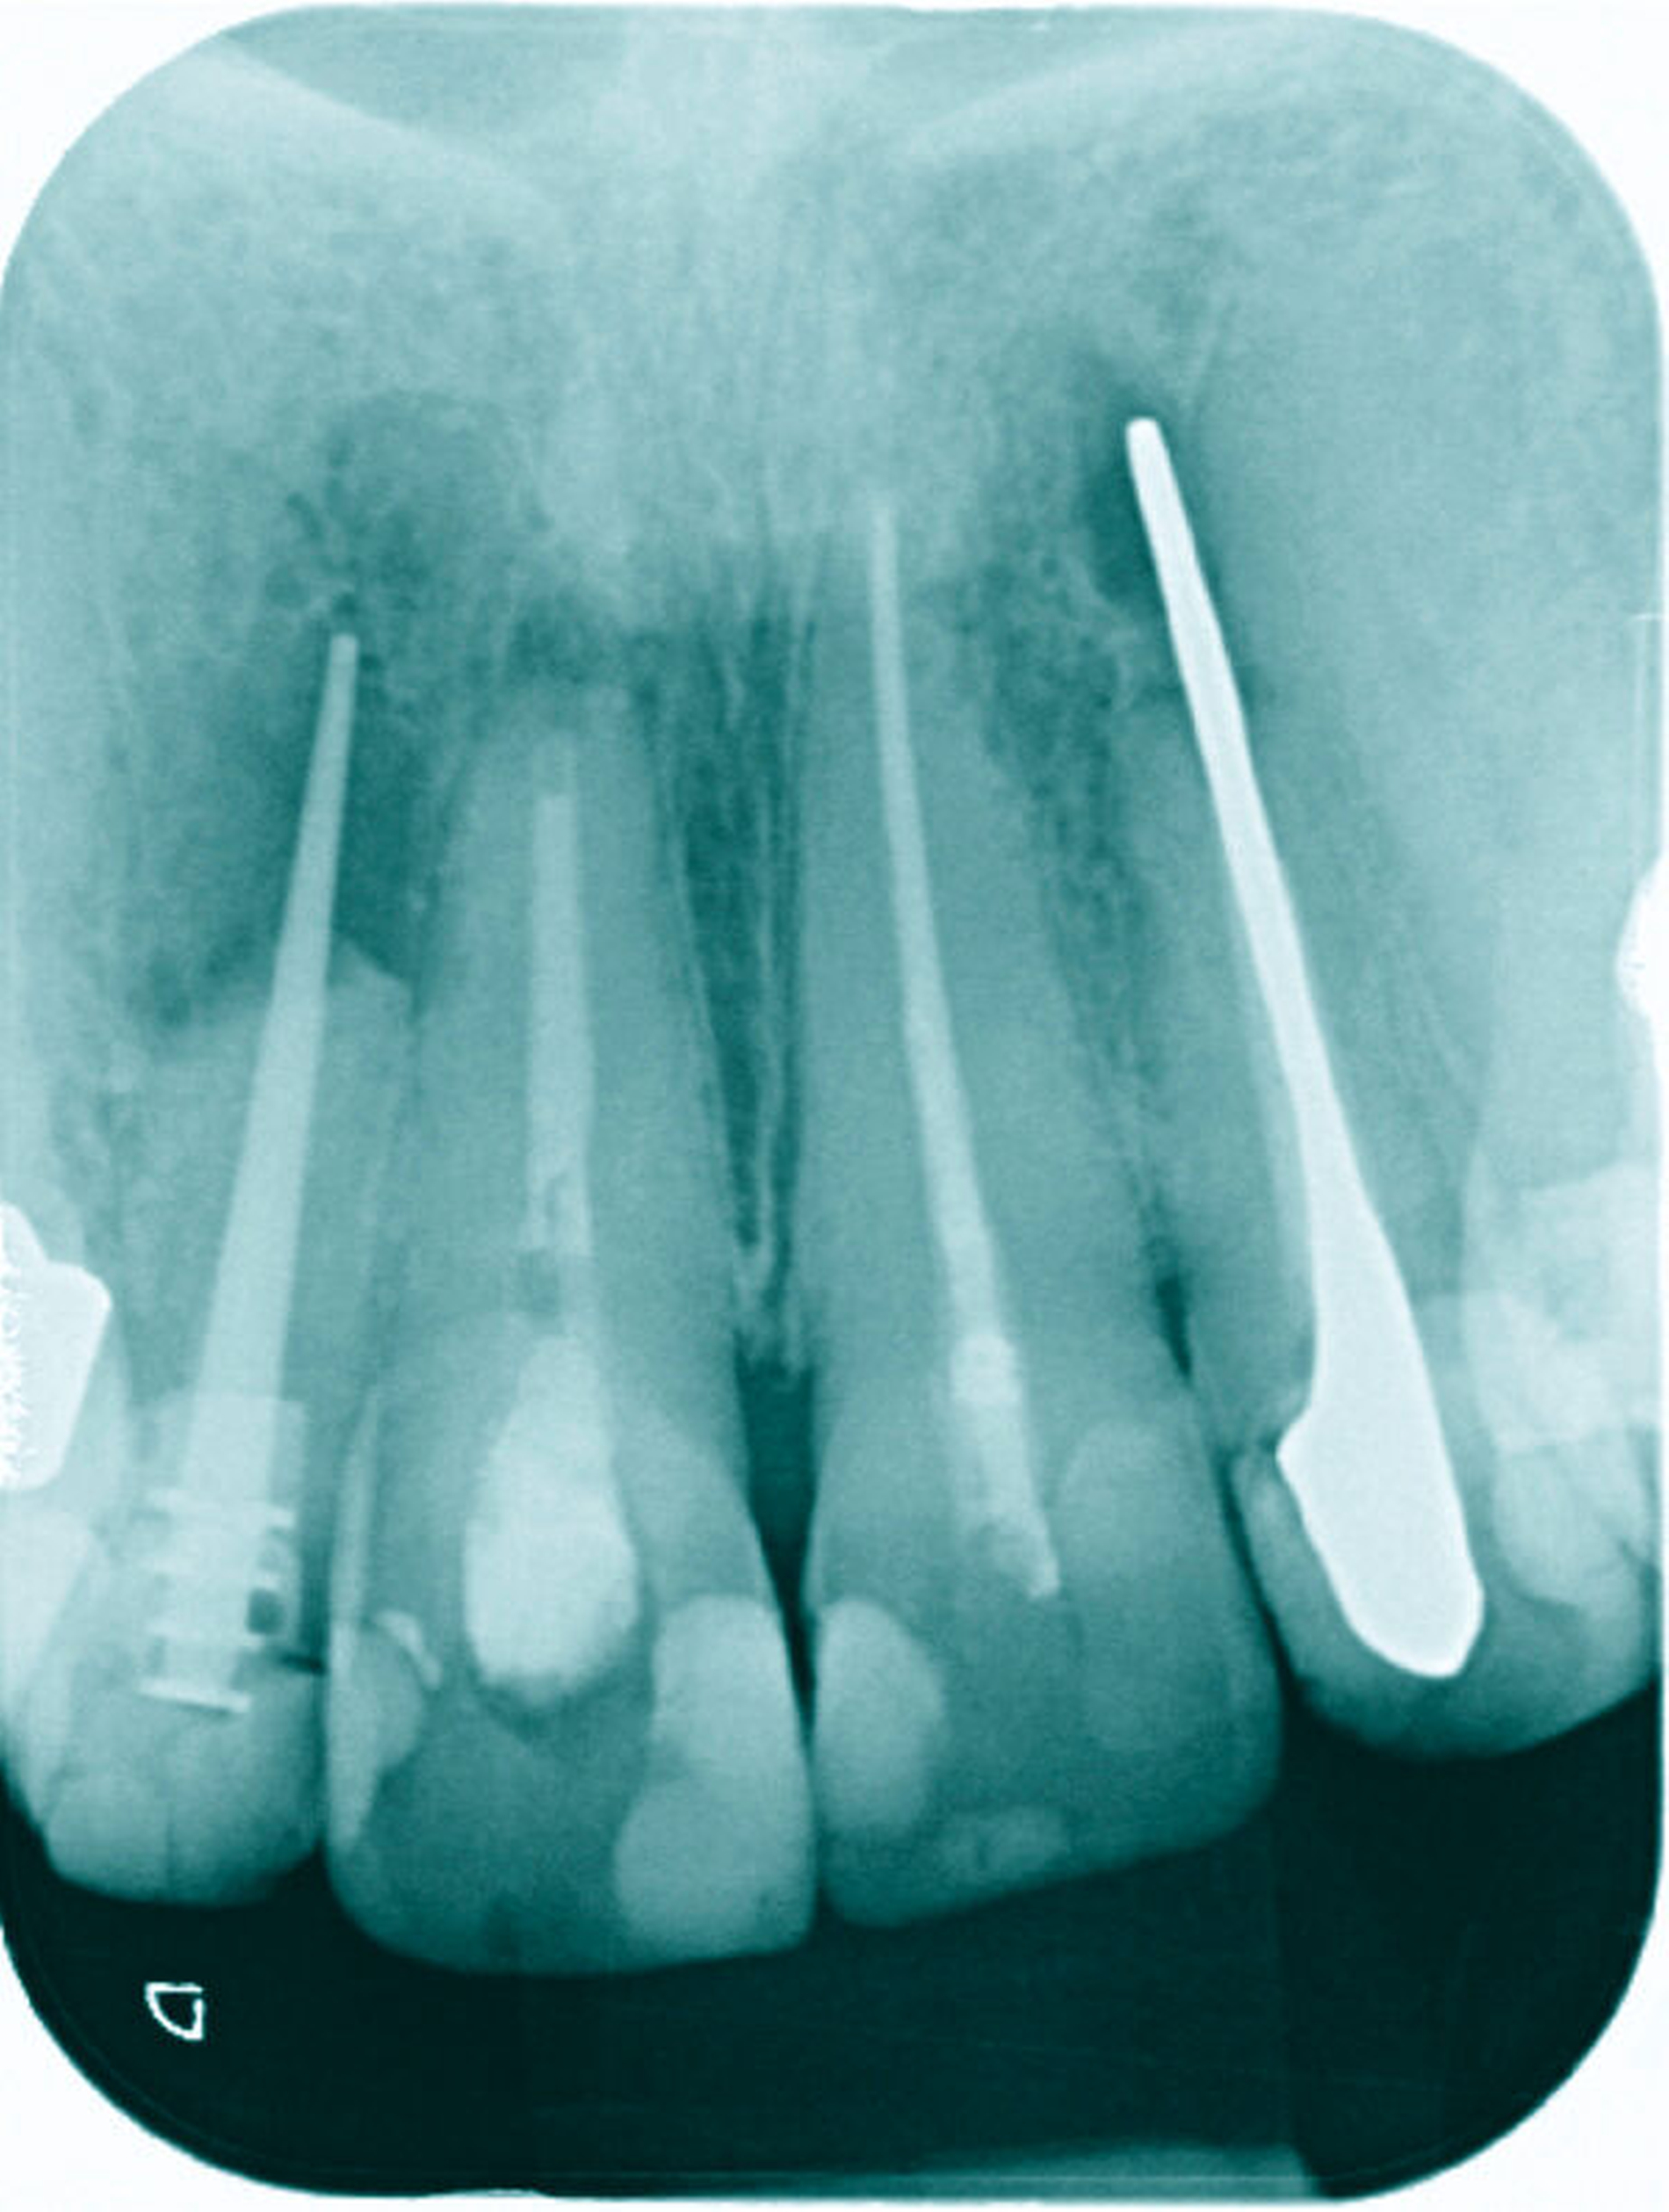

25 Prozent aller Wurzelkanalbehandlungen finden an Frontzähnen statt. Im Vergleich zu Molaren und Prämolaren werden an Frontzähnen danach häufiger Revisionen, Wurzelspitzenresektionen und Extraktionen nötig [Rädel et al., 2014]. Trotz scheinbar einfacher Anatomie treten im Verlauf von Wurzelkanalbehandlungen Komplikationen auf, die wiederholte endodontische oder endo-chirurgische Therapien nach sich ziehen können – mit unsicherer Prognose (Abbildung 2). Eine möglicherweise verkannte Ursache ist die nicht immer leicht zu erkennende variable Anatomie des Wurzelkanalsystems und die im Verlauf der Alterung von Pulpa und Dentin sich vollziehenden Veränderungen dentaler Gewebe [Ørstavik & Pitt-Ford, 2008].

Von klinischer Bedeutung sind bei seitlichen Schneidezähnen (und Eckzähnen) mehrere anatomische Besonderheiten. So können die nach distal gerichteten apikalen Krümmungen eine vollständige Erweiterung und Desinfektion erschweren. Die apikale Begradigung und Verlagerung des apikalen Foramens mit iatrogener Vergrößerung, die Verblockung mit Debris oder die Fraktur von Wurzelkanalinstrumenten sind keine seltenen Komplikationen – sie können das Ergebnis der Wurzelkanalbehandlung negativ beeinflussen (Abbildung 12).